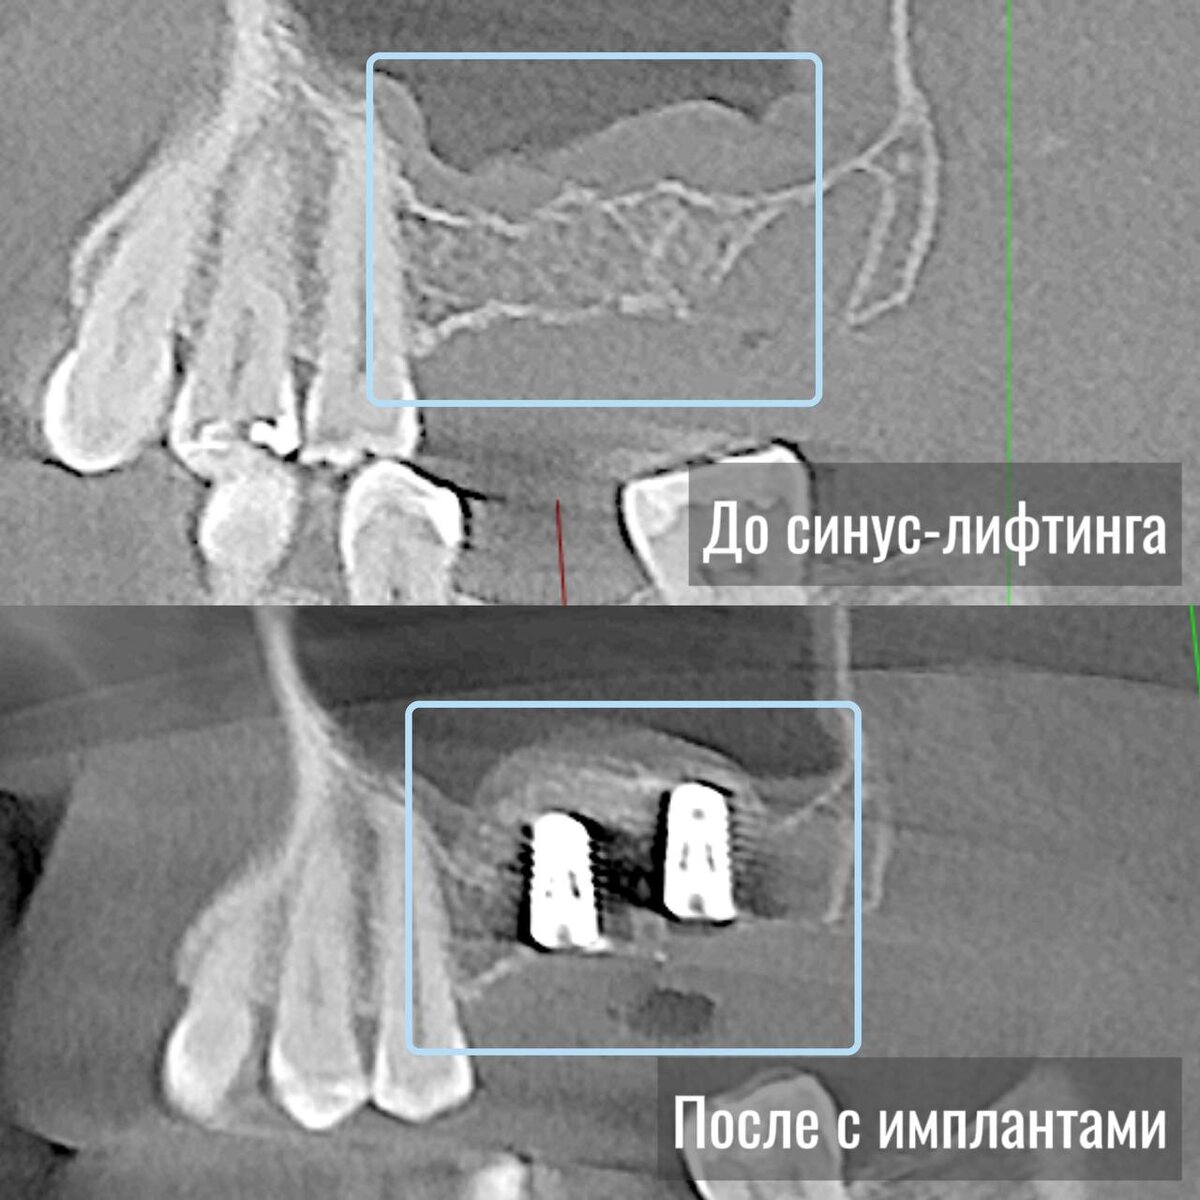

В прошлом посте мы говорили о костной пластике, а сейчас разберем, что такое синус-лифтинг. Это манипуляция, при которой тоже добавляют количество костной ткани, но именно на верхней челюсти. Называется она так потому, что рядом располагаются пазухи (синусы). Синус-лифтинг или поднятие синуса – это хирургический процесс, который стоматологи используют для увеличения количества костной ткани в области верхней челюсти, в районе задних верхних зубов. Это может быть необходимым, когда пациенту требуется имплантация, но в данном месте недостаточно костной ткани для устойчивости и надежной фиксации имплантатов. В ходе данной манипуляции врач создает доступ к пазухе, мягко поднимает слизистую оболочку и добавляет костный материал в образовавшееся пространство. Это обеспечивает дополнительный объем для установки имплантатов спустя 4-6 месяцев поле имплантации! #хирургия #имплантация